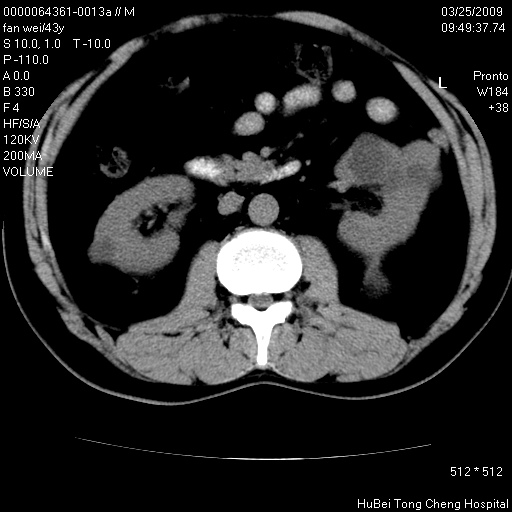

双肾ct轴位平扫+增强扫描(层厚10mm,螺距1.0,重建间隔10mm),图像如下:

多囊肾的影像诊断标准:有阳性家族史,年龄<30岁,单侧或双侧肾脏有两个肾囊肿;30~59岁,两侧肾脏各有两个肾囊肿;60岁以上,每侧肾脏有4个囊肿。敏感性和特异性达86%和80%。

此病例影像诊断符合,要结合家族史,腰痛、血尿、尿路感染史,有无高血压等综合判断,如无相应的临床症状,本身病变也无意义了(个人观点)

左肾体积变大,支持多囊肾。

双肾多发性囊肿   脂肪肝

囊肿数得清,肾功能正常,考虑多发肾囊肿.另外,右肾后极突向肾周间隙的那个病灶是不是错构瘤,请楼主调窗看看.